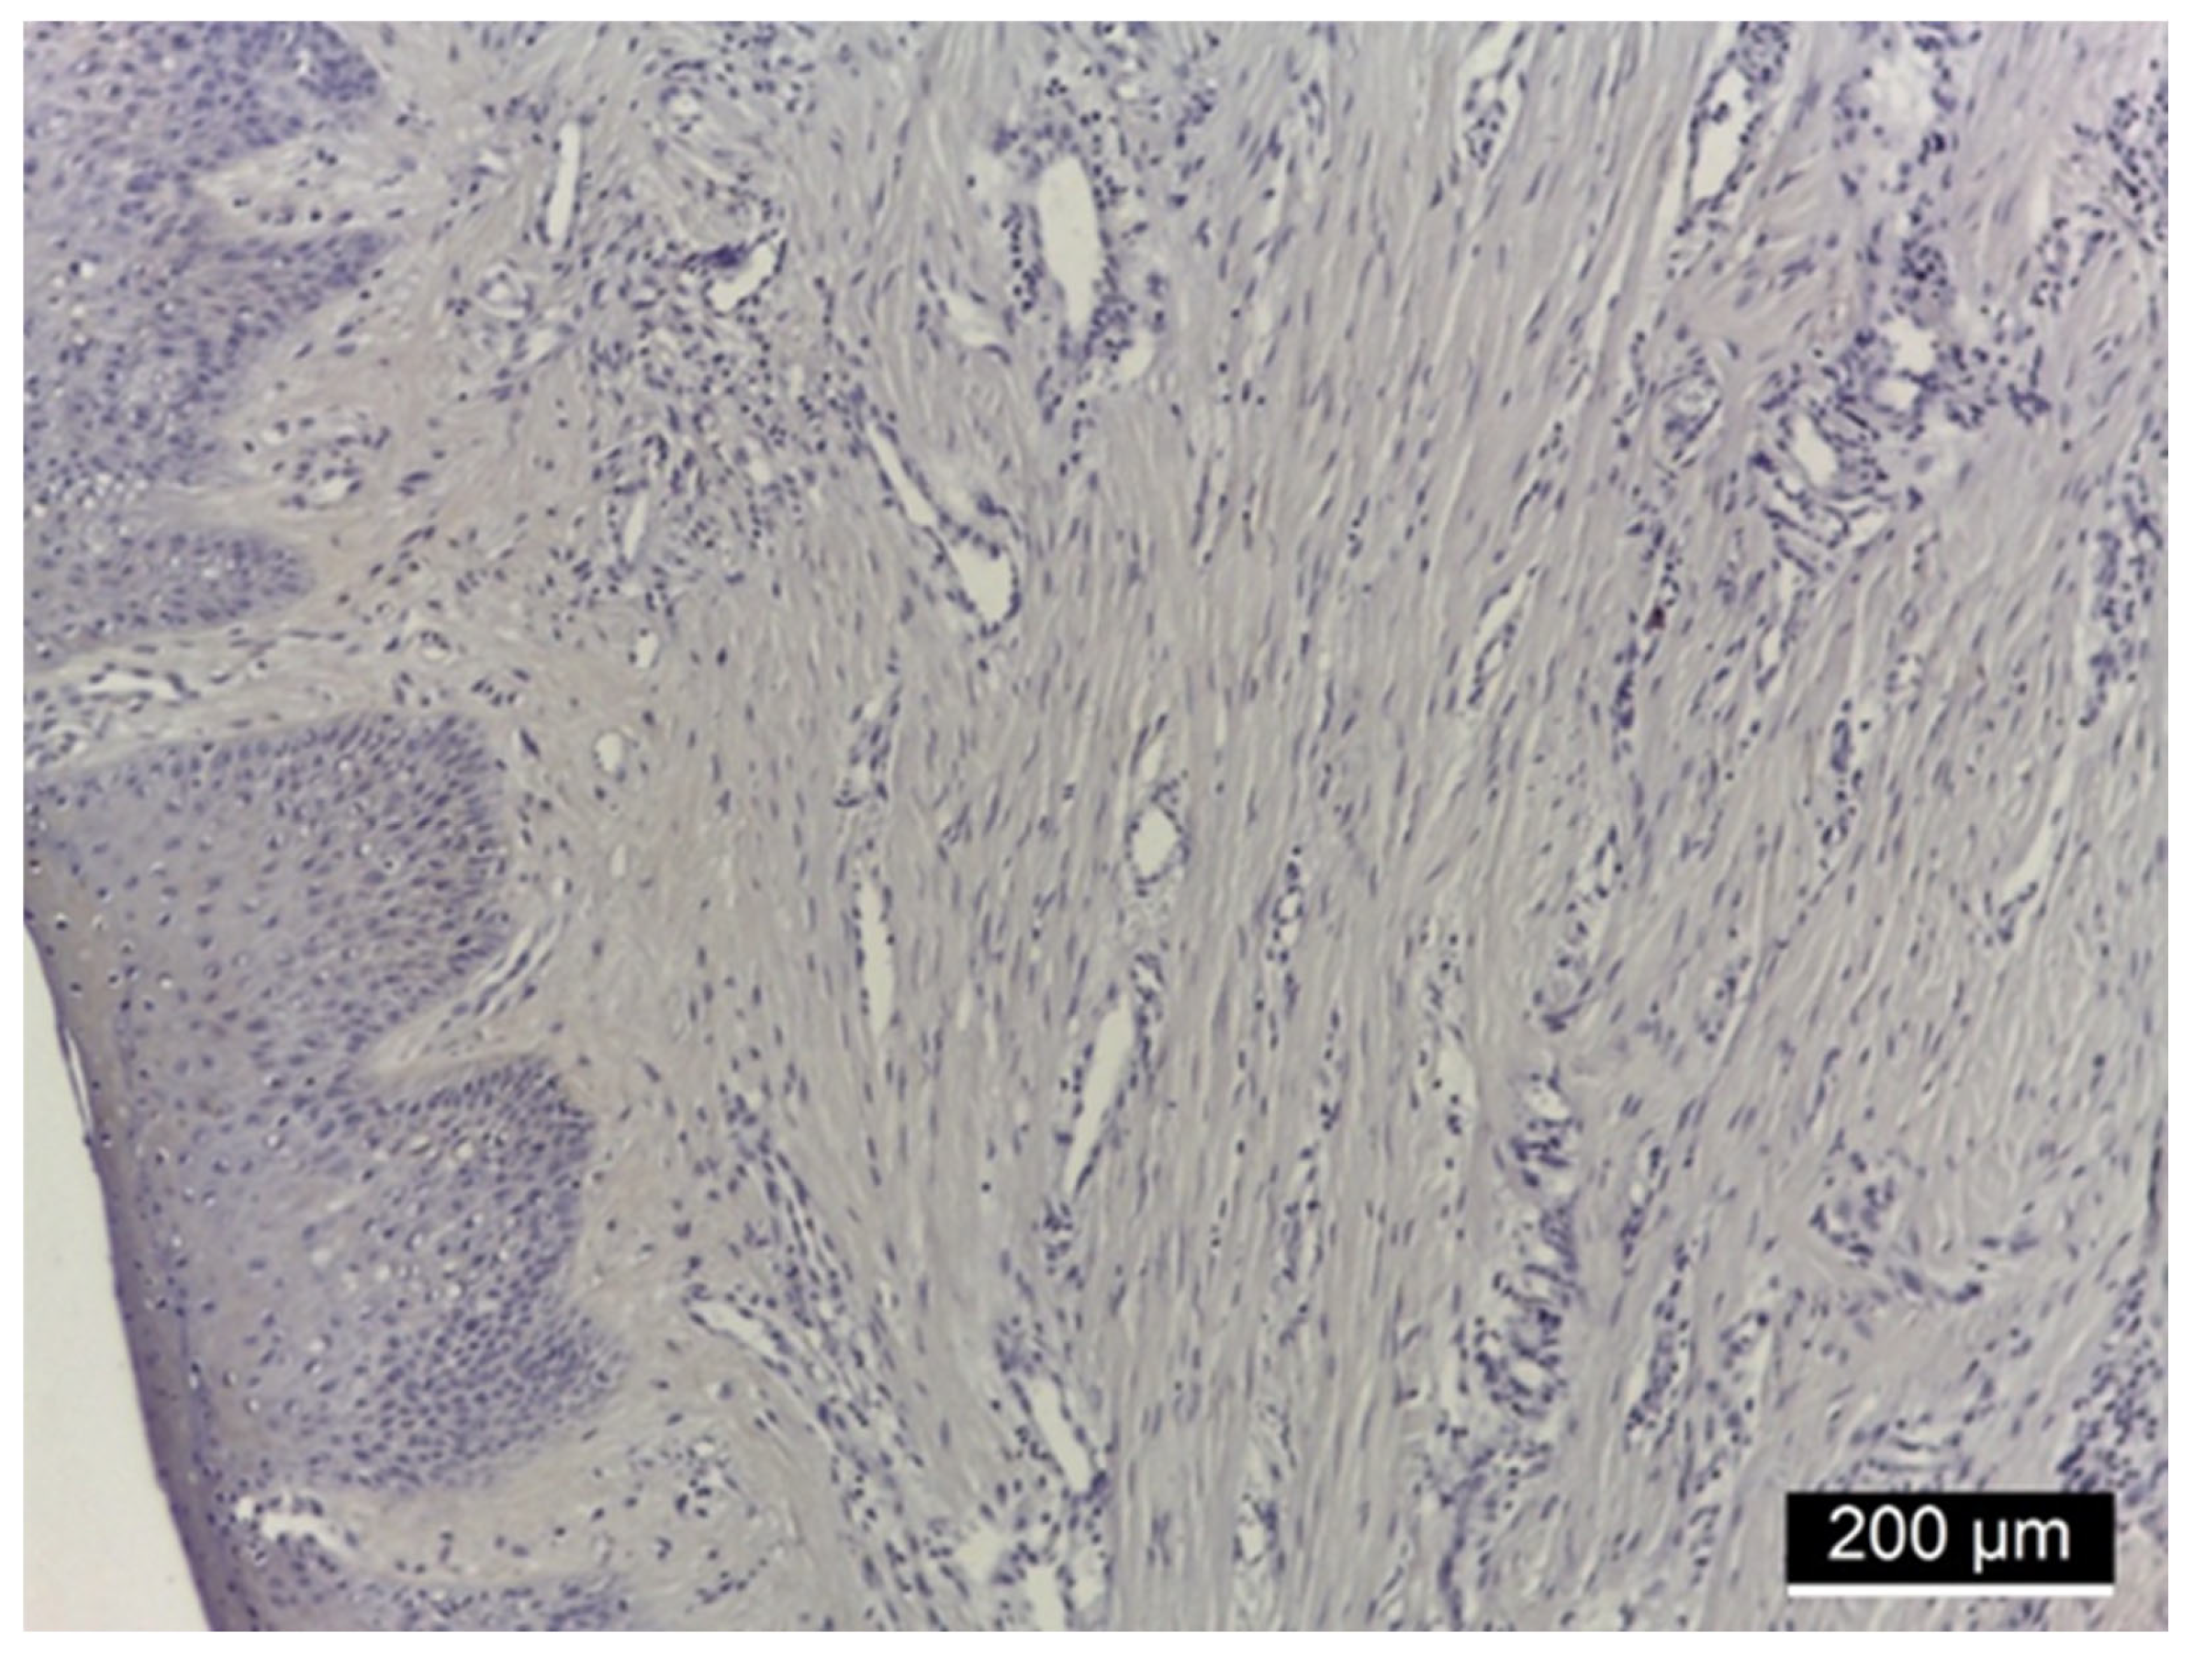

3.3. MMP-2 Immunoreactivity

4.2. MMP-2 Immunoreactivity